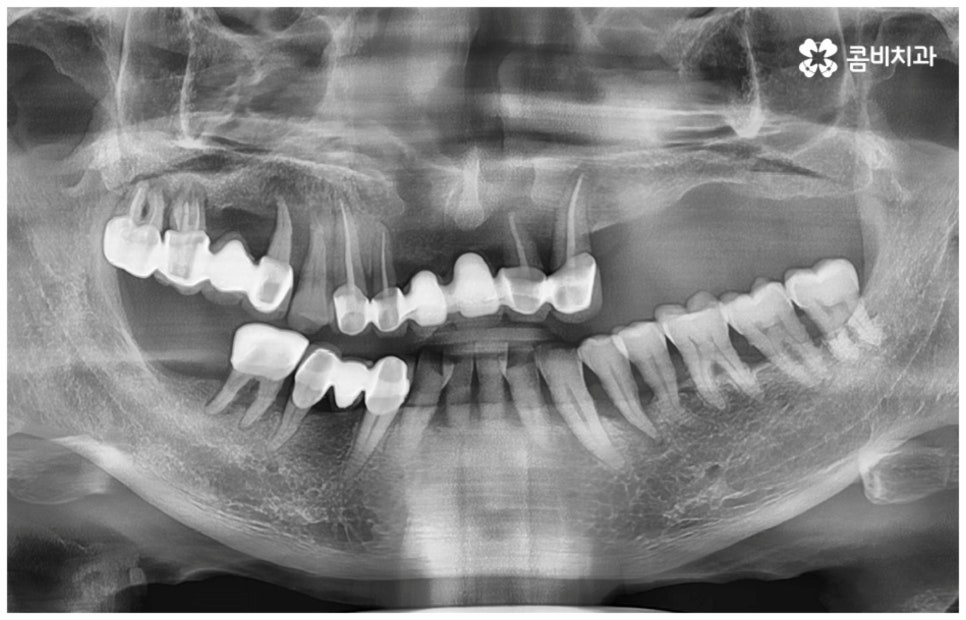

그러나 노화나 구강 질환을 원인으로 한 경우에는 식립 절차가 좀 더 복잡해 질 수 있는데요. 잇몸병을 예로 들어 생각해 보면 자연스러운 노화 및 관리 소홀로 인해 치아 주변 조직 (잇몸, 치주인대, 치조골 등) 에 염증 반응이 생기는 병인 치주 질환이 많이 심해졌을 때 상황에 따라 해당 자연 치아를 살리지 못하고 발치를 해야할 수도 있는 거예요. 이렇게 치주질환을 이유로 임플란트 식립을 진행할 때에는 식립 성공률을 높이고 임플란트수명 을 늘리기 위해 먼저 치주질환 치료를 선행해 줘야 하며, 환자분들의 상황에 따라 뼈이식 또는 상악동 거상술을 통해 잇몸뼈를 보충해 줘야 할 수도 있어요. 치조골이 이미 많이 녹아 있거나 병증이 극심하다면 임플란트 식립 난이도가 매우 높아지거나 때로는 불가능해 질 수 있기 때문에 다양한 임상 경험을 통해 풍부한 노하우를 가지고 있는 의료진에게 진단 및 치료를 받는 것이 굉장히 중요한 포인트라고 할 수 있습니다.